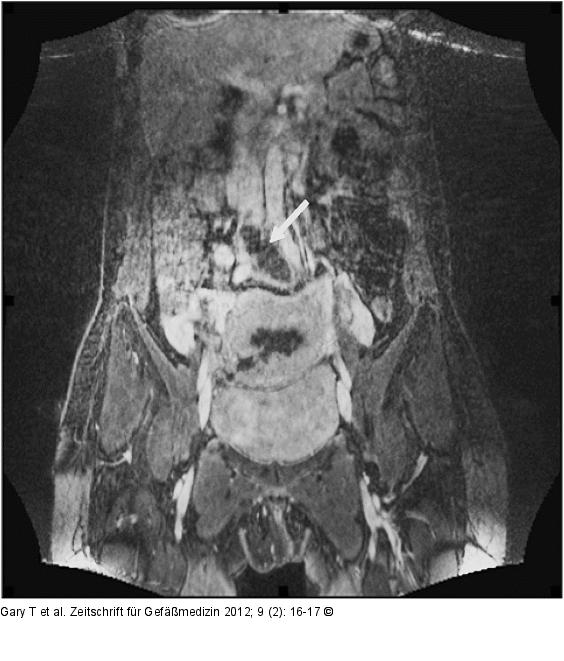

Abbildung 1: VCI - Thrombose

Thrombose der VCI in der linken Beckenetage fortgesetzt. |